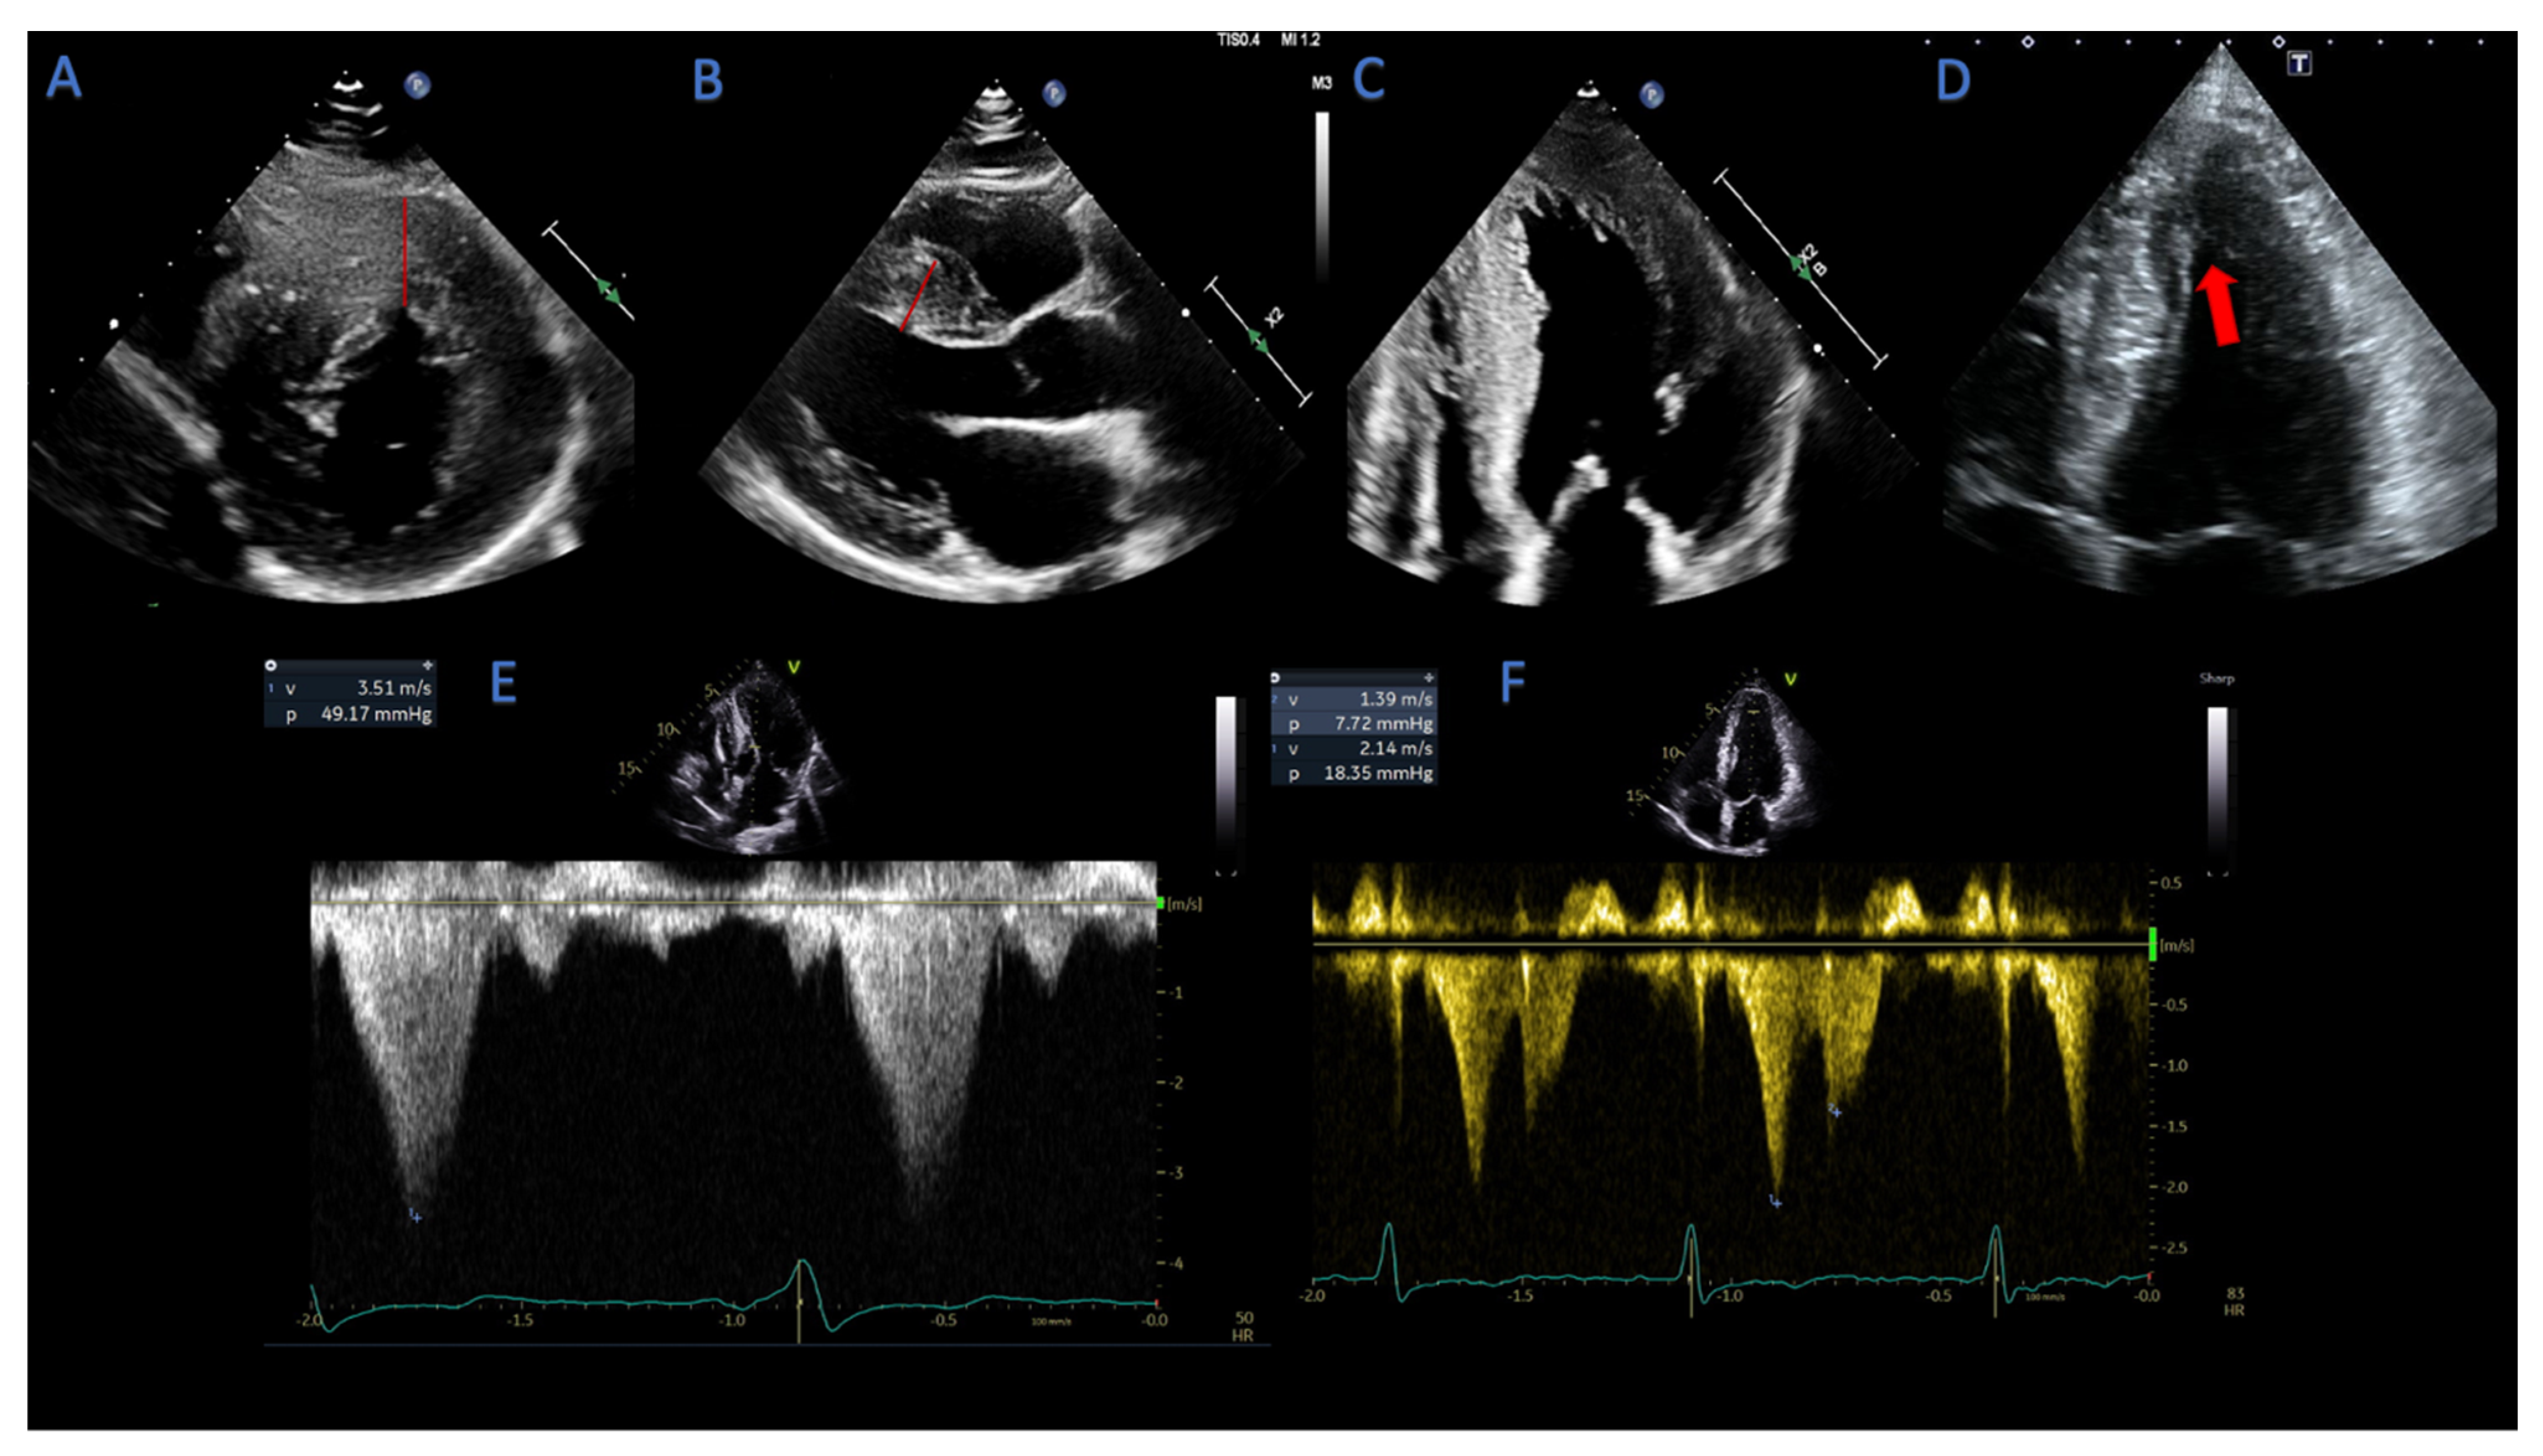

2.1.4. Assessment of LVOT- and Mid-Cavity Obstruction